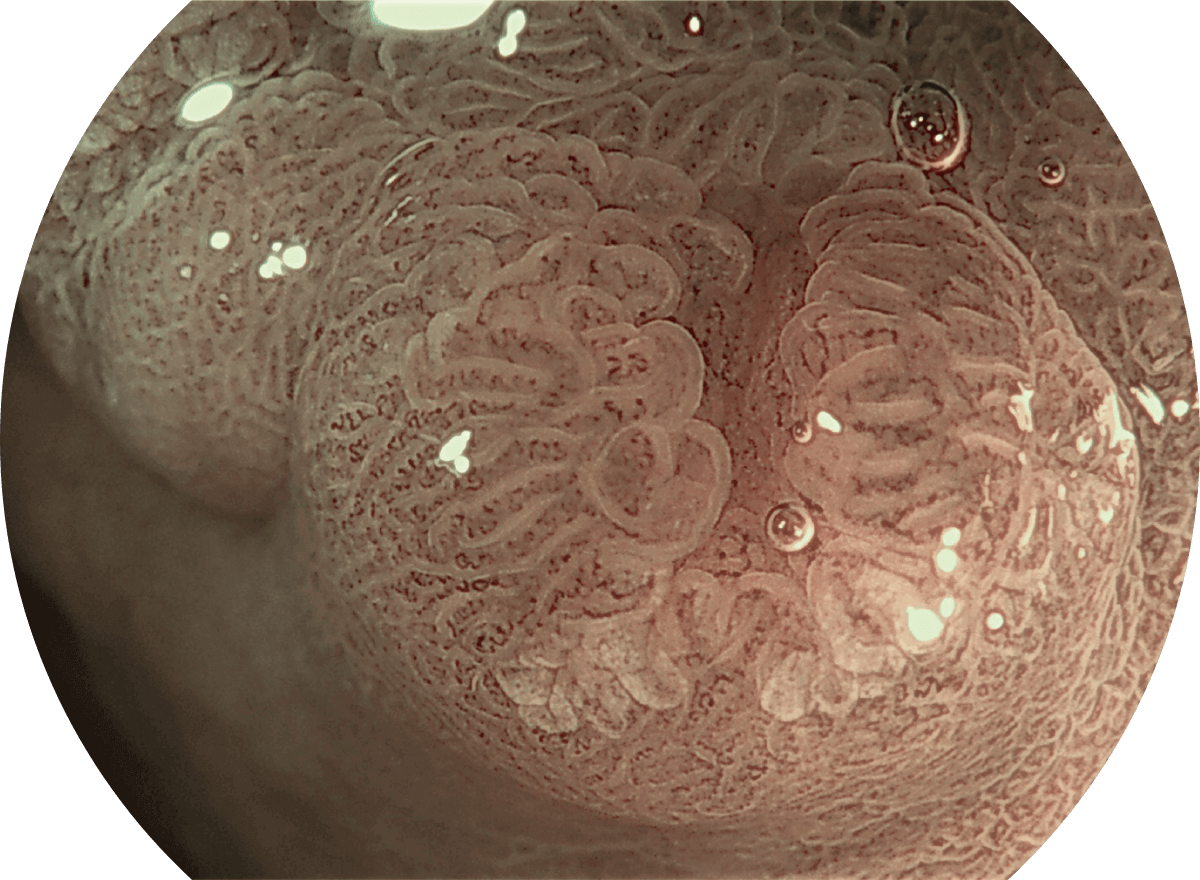

VIST+放大

具有连续变焦功能,图像可通过变焦拨杆实现广角与长焦的切换。